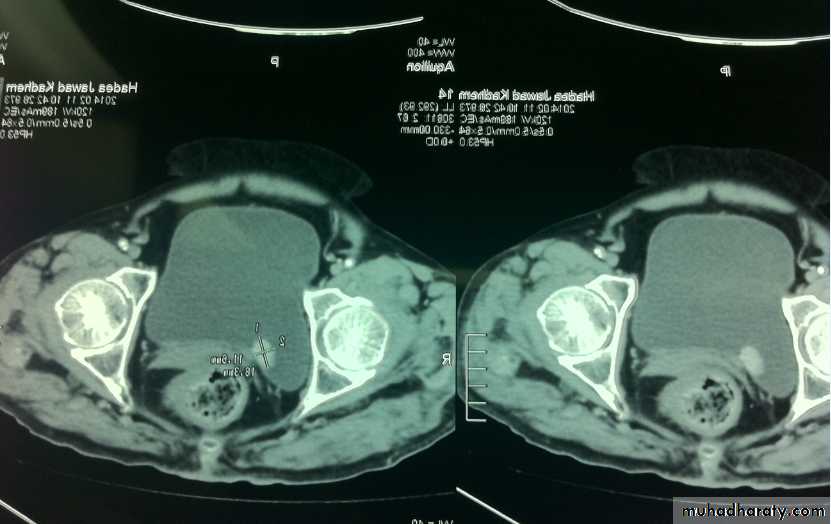

Also to prevent retention of urineWhat's this imaging study?What the abnormal finding?

Wilms tumor deviating the kidney ant. Upward

Big should be reduced by chemo then surgeryWhat's this test?